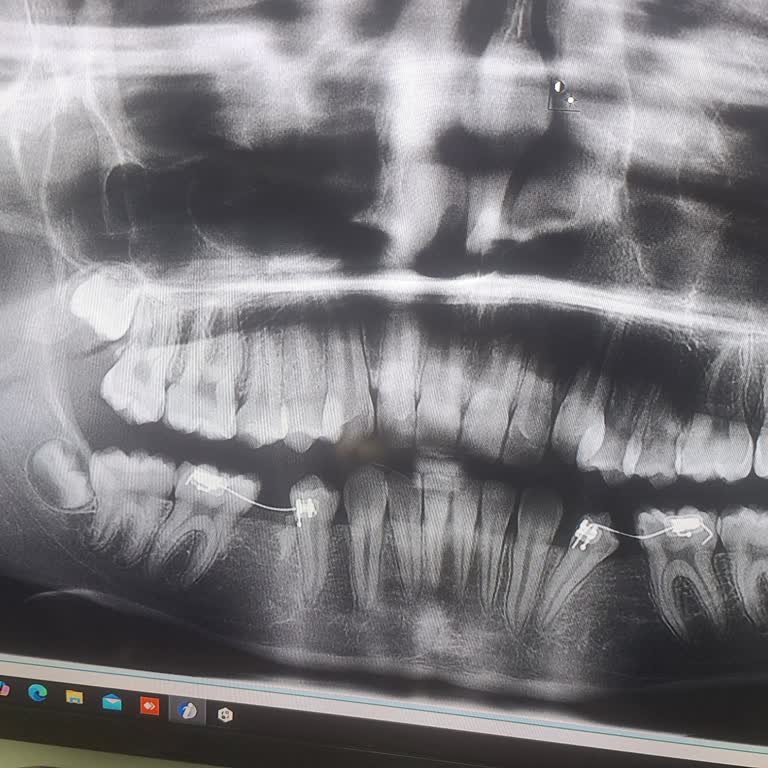

09.12.2025 tarihinde kızımın 16 numaralı kaplama dişi düştüğü için İstanbul Bağcılar’daki Özel Bağcılar Ağız ve Diş Sağlığı Merkezi’ne götürdüm. Muayene sırasında doktor H**** Ş****, alt dişinin de kaplama olduğunu, kızımın yaşı büyüdüğü için her iki dişin de zirkonyum kron ile yenilenmesi gerektiği...